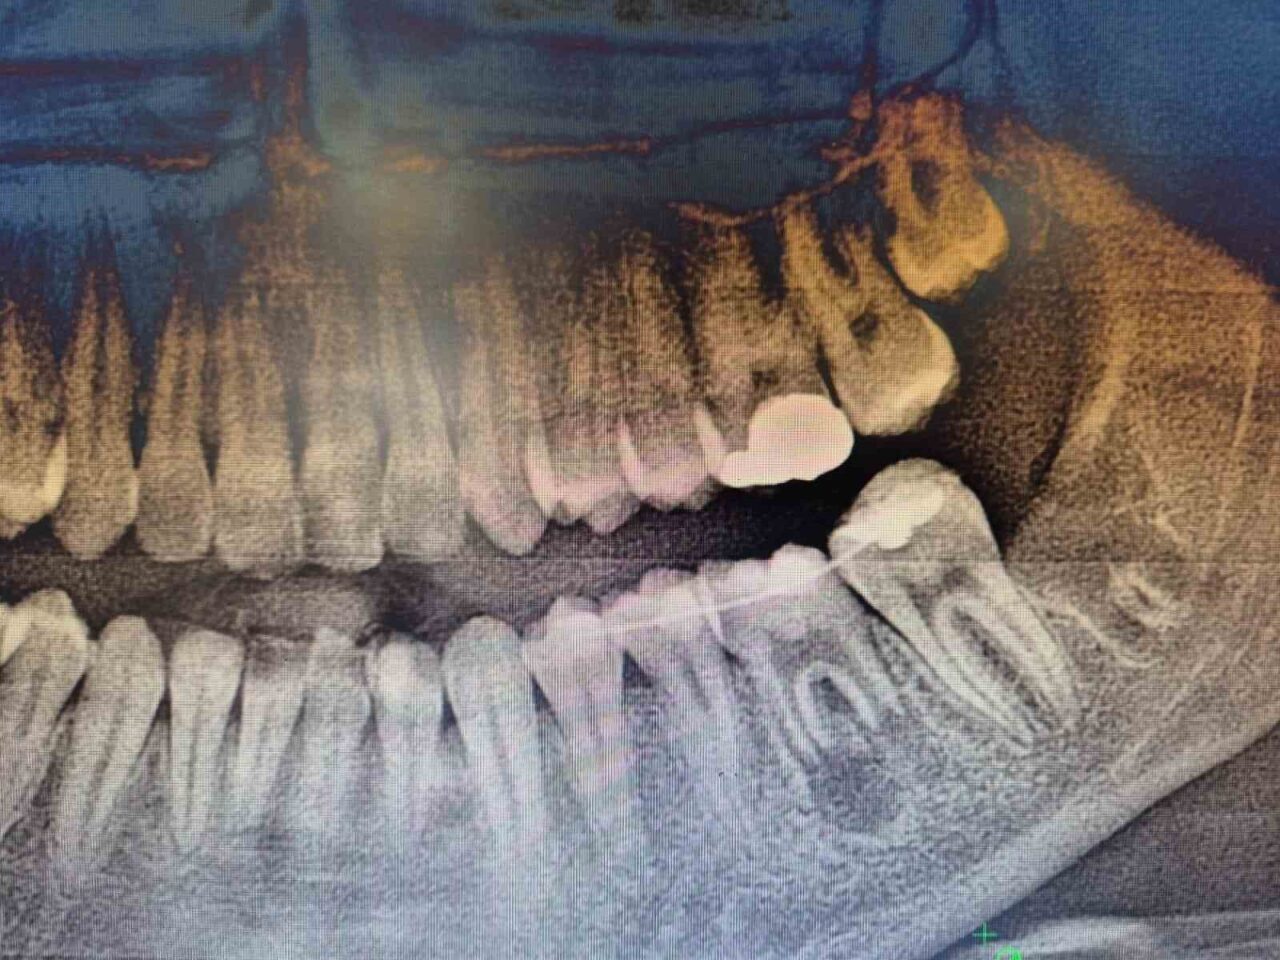

Hastanın daimi azı dişi, ileri düzey çürük nedeniyle çekilmişti. Yaşı itibarıyla çene gelişimi henüz devam eden hastada, geleneksel implant tedavisi uygun bulunmadı. Uzman ekip, hastanın ağız içinde gömülü durumda bulunan yirmi yaş dişini cerrahi bir işlemle çıkararak, çekilen dişin yerine nakil etti.

Operasyon sürecinde, dişin yerinde sağlıklı bir şekilde tutunabilmesi için hastanın kendi kanından elde edilen PRF (Platelet Rich Fibrin) biyomateryali, diş yuvasına yerleştirildi. Bu doğal yöntem, doku iyileşmesini hızlandırdığı gibi hücre yenilenmesi üzerindeki olumlu etkisi ile dikkat çekiyor. Hastanın kendi dişinin kullanılması, görünüm, uyum ve fonksiyon açısından önemli avantajlar sunarken, vücut tarafından kabul edilme oranı yüksek olduğundan, uzun vadeli başarı olasılığı da artıyor.